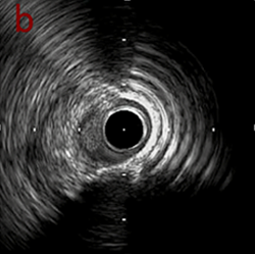

IVUS imaging

IVUSでは8時方向からPD枝がはいいてくる。

PreのIVUSではaの部位のみlipid plaqueを認め削ることでdistal embolismのリスクがあり、そのほかは270度の偏心性石灰化であるがwire biasは良好。

OAS low speedによる引きを赤線の区間行う方針とした。